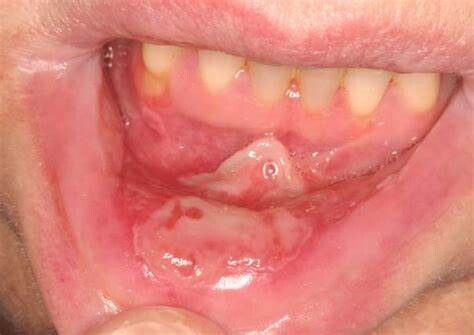

Things to Know about Mucositis

Mucositis, or mouth sores, is a common side effect of chemotherapy, radiation therapy, and bone marrow transplant. The mouth is one of the most sensitive parts of the body and is especially vulnerable to cancer treatment side effects.

Mouth sores can cause pain, poor nutrition (if it hurts too much to eat), and infections. They can affect your quality of life and can lead to limits on your chemotherapy doses. You can help prevent mouth sores and mouth swelling by eating well and having good oral hygiene.

What are some signs of mucositis?

Red, shiny, or swollen mouth and gums

Blood in the mouth

Sores in the mouth or on the gums or tongue

Soreness or pain in the mouth or throat

Difficulty swallowing or talking

Feeling of dryness, mild burning, or pain when eating food

Soft, whitish patches or pus in the mouth or on the tongue

Increased mucus or thicker saliva in the mouth

Mouth sores generally appear 5–10 days after the start of chemotherapy and last anywhere from 1–6 weeks.